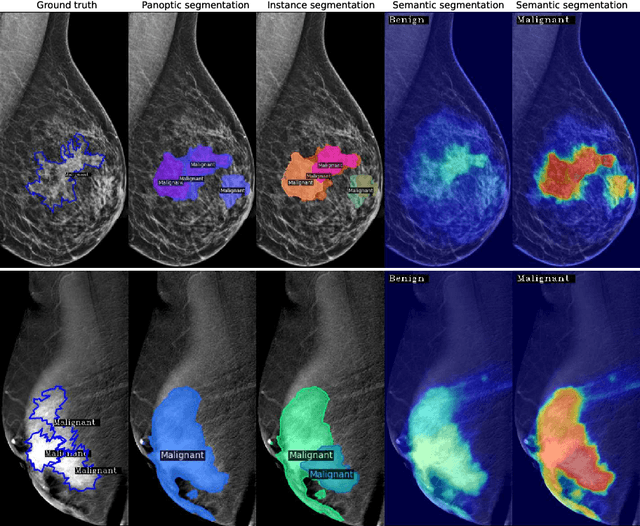

Mammography is crucial for breast cancer surveillance and early diagnosis. However, analyzing mammography images is a demanding task for radiologists, who often review hundreds of mammograms daily, leading to overdiagnosis and overtreatment. Computer-Aided Diagnosis (CAD) systems have been developed to assist in this process, but their capabilities, particularly in lesion segmentation, remained limited. With the contemporary advances in deep learning their performance may be improved. Recently, vision-language diffusion models emerged, demonstrating outstanding performance in image generation and transferability to various downstream tasks. We aim to harness their capabilities for breast lesion segmentation in a panoptic setting, which encompasses both semantic and instance-level predictions. Specifically, we propose leveraging pretrained features from a Stable Diffusion model as inputs to a state-of-the-art panoptic segmentation architecture, resulting in accurate delineation of individual breast lesions. To bridge the gap between natural and medical imaging domains, we incorporated a mammography-specific MAM-E diffusion model and BiomedCLIP image and text encoders into this framework. We evaluated our approach on two recently published mammography datasets, CDD-CESM and VinDr-Mammo. For the instance segmentation task, we noted 40.25 AP0.1 and 46.82 AP0.05, as well as 25.44 PQ0.1 and 26.92 PQ0.05. For the semantic segmentation task, we achieved Dice scores of 38.86 and 40.92, respectively.